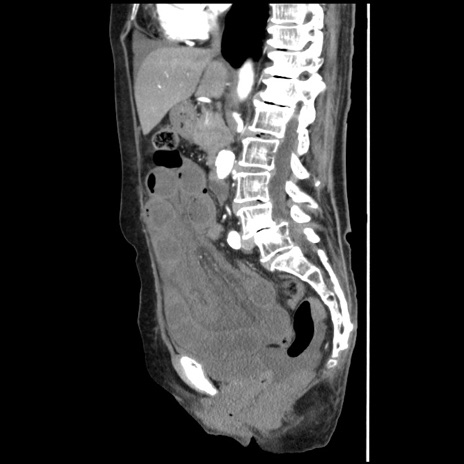

冠状断像

【症例】80歳代女性

【主訴】腹痛

【現病歴】8時間前から腹痛あり来院。

【既往歴】糖尿病、脂質異常症、子宮体癌にて子宮全摘術

【身体所見】意識清明・会話良好だが腹痛で苦悶様、全腹部にわたって反跳痛と圧痛あり

【データ】WBC 13600、CRP 0.14、LDH 224、CK 90